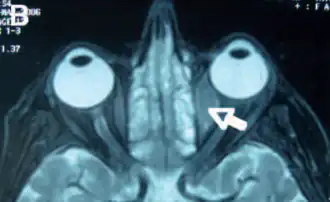

Орбитальная лимфома является распространенным типом неходжкинской лимфомы, что происходит вблизи глаза или в глазе. Общие симптомы включают в себя снижение зрения и увеит. Орбитальная лимфома может быть диагностирована с помощью биопсии глаза и обычно лечится с помощью лучевой терапии или её комбинации с химиотерапией.

Основные видимые симптомы глазной лимфомы включают экзофтальм и видимую массу в глазе. Другие симптомы связаны с масс-эффектом.